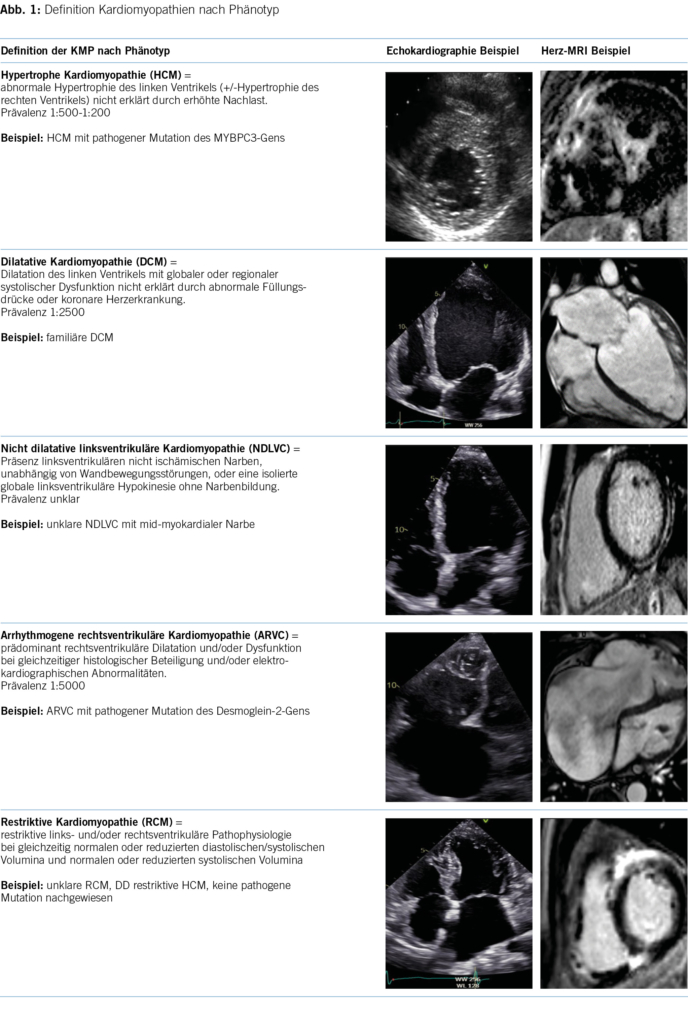

Folgendes Fallbeispiel eines 49-jährigen, männlichen Patienten mit progredienter Dyspnoe ist eine Illustration des diagnostischen Leitfadens. In der medizinischen Vorgeschichte sind eine unklare Niereninsuffizienz und ein bilaterales Karpaltunnelsyndrom bekannt. Die Familienanamnese ist bezüglich kardiovaskulärer Erkrankungen unauffällig. In der körperlichen Untersuchung fallen vor allem ein verbreiteter Herzspitzenstoss und ein vierter Herzton auf. Die pathologischen Werte in der Laboruntersuchung sind: Kreatinin 130umol/l, Troponin 46ng/l, NTproBNP 1700ng/l. Im 12-Kanal-EKG werden ein normokarder Sinusrhythmus, normale Zeitindices, ein Linkslagetyp, ST-Senkungen inferior und diskrete periphere Niedervoltage beobachtet. Die Echokardiographie zeigte einen konzentrisch verdickten linken Ventrikel mit erhaltener systolischer Funktion und schwerer diastolischer Dysfunktion mit restriktivem Füllungsmuster. Im Herz-MRI wurde eine diffuse, teils transmurale Fibrose beider Ventrikel und Vorhöfe dargestellt (Abbildung 4). Nach dieser Standortbestimmung gehen wir von einem Mischphänotyp der HCM und RCM aus. Die Bildgebung ist in diesem Fall sehr suggestiv für eine kardiale Amyloidose. Für die weitere Differentialdiagnose der Amyloidose wurden weitere Laboruntersuchungen (Immunfixation Serum und Urin) und eine weitere Bildgebung (99mTc-DPD- Szintigraphie) veranlasst. Infolge fehlender Hinweise für eine Plasmazelldyskrasie und Nachweis einer ausgeprägten Radionukleidanreicherung im linksventrikulären Myokard konnte die Diagnose einer Transthyretin Amyloidose gestellt werden. Aufgrund des sehr frühen Krankheitsauftretens erfolgte auch eine bioptische Sicherung der Diagnose mittels Endomyokardbiopsie. Nach einer genetischen Testung konnte eine genetische Form der Transthyretin Amyloidose ausgeschlossen werden, was wiederum für die Familie wichtig ist. Die genaue Stellung der Diagnose ermöglichte den Beginn einer Transthyretin-stabilisierenden Therapie.